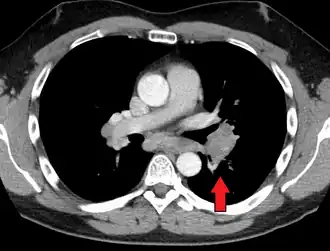

-

Hilar adenopathy especially on the person's left (AP CXR)

Hilar adenopathy especially on the person's left (coronal CT)

Hilar adenopathy especially on the person's left (transverse CT)